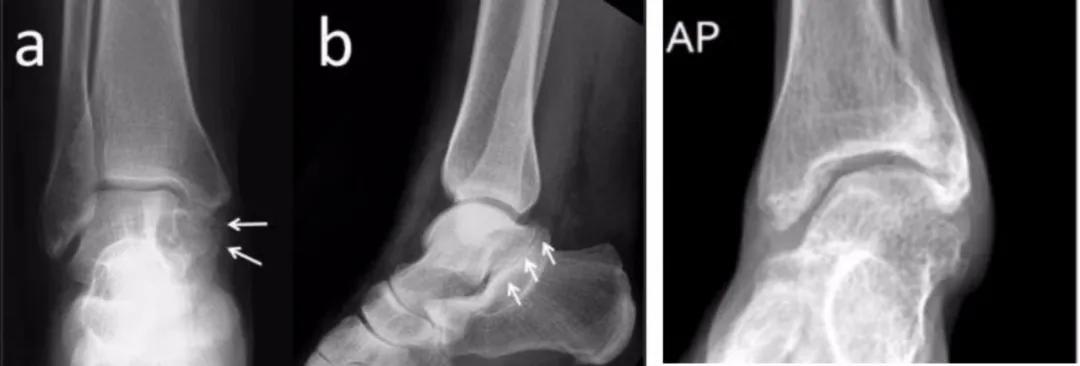

■ X线表现

常见的X线表现为:

足负重侧位可见距骨上方喙突样骨赘,距下后关节面形态异常,中关节面消失征,C型征。

踝负重关节正位可见内踝骨性突起。

还可能存在球窝样踝关节(Ball-Socket ankle)、踝外翻。

图 | 跟距骨桥的X线表现